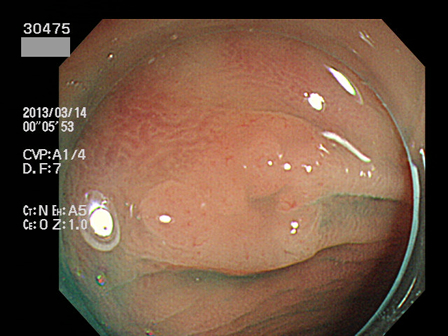

30400 30402 30405 30407 30408 30409 30413 30417 30419 30420 30422 30424 30428 30429 30432 30434 30442 30443 30444 30445 30446 30450 30451 30453 30458 30463 30464 30465 30467 30471 30472 30473 30474 30475 30476 30483 30487 30490 30492 30494 30496 30497 30499・・・・・・・の43名

上記100名より抽出した平坦・陥凹型腺腫(=癌化の危険が高いが見落としやすい病変)の内視鏡写真